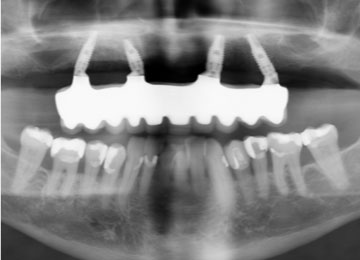

Подготовительный этап

Чтобы получить все данные о строении костной ткани, расположении сосудов, нервов и синусовых пазух, необходимо пройти обследование: сделать компьютерную томограмму, рентгеновский снимок, исключить противопоказания, связанные с заболеваниями крови и т. д. По плану лечения отмечаются проблемы, которые можно устранить, например, кариес, воспаление десен, пародонтоз. Также мы проводим отбеливание зубов, как дополнительную процедуру.

Предварительное 3D-моделирование челюсти дает возможность составить представление, где будут расположены импланты и как они будут выглядеть.

- Хирург имплантолог и ортодонт подбирают тип импланта.

- Создается прототип протеза, а на десне определяется точки вхождения и направления импланта, параметры, касающиеся размера и угла наклона.